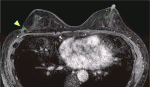

早期乳癌のRFAを「体表面から乳房内病変に対して画像ガイド下にラジオ波電極針を穿刺し,病変にラジオ波による焼灼を行う手技」と定義する.医療技術の概要は図5に示す.

5)焼灼範囲:腫瘍縁から1cmのマージンを目標とし,ニードルポジションを設定する.焼灼中の超音波画像にて腫瘍の不明瞭化とマイクロバブルの範囲を確認し,十分な焼灼エリアを確保する(図7).